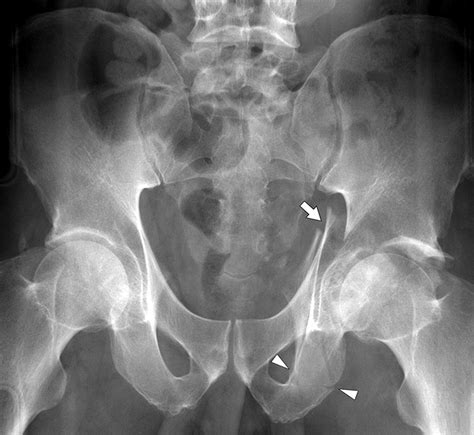

• Standard Radiographs: Pelvic AP and Judet views to assess the general orientation of the pelvis.

• CT Scans: The gold standard. A CT scan provides a detailed view of the articular surface and the displacement of fracture fragments.

Because the acetabulum is complex in shape, clinicians use specific classification systems to describe the injury pattern. The most widely recognized system is the Letournel-Judet classification, which divides fractures into five "elementary" types and five "associated" types. Recognizing the specific pattern is crucial for determining whether conservative management or surgical intervention is required.